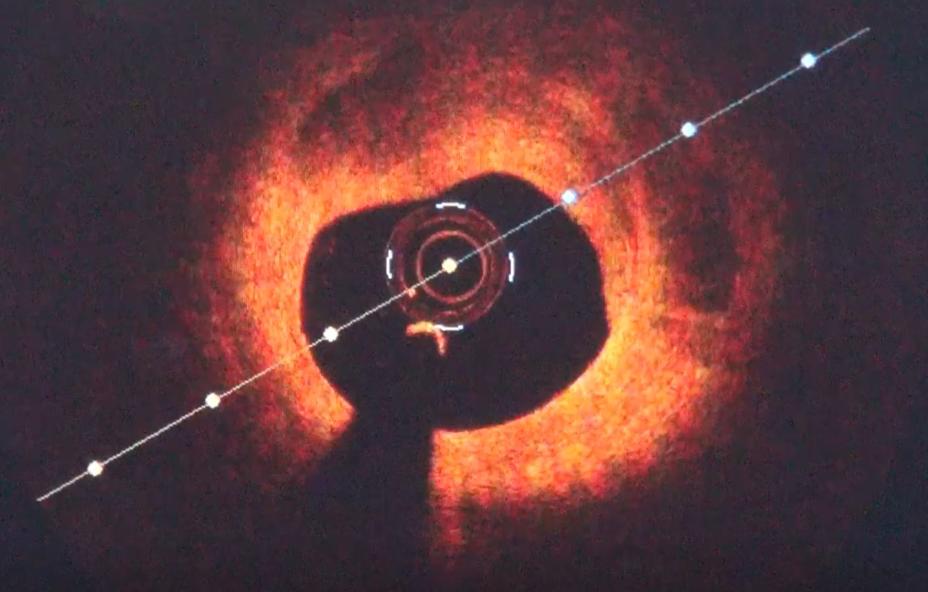

经过和老宋的沟通,心脏中心团队决定针对这个部位,使用血管内影像学技术,就是在造影的基础上,通过原来血管的通道,把一个血管内的红外线相干成像的探头,输送到冠脉血管里,更精细地查看狭窄部位。

从横截面上可以看到,大概是在这个位置,对应造影上看到的60%左右的狭窄区域。

这部分的横截面积,只有2.71平方毫米。

而按照指南规定,最小能够接受的横截面积是4个平方毫米。他都已经远远的不达标。

管径太细,无论血流有多快,压力有多大,心肌也没办法得到所需要的血流量。毫无疑问,这个所谓的狭窄40%~50%的部位,必须要处理。